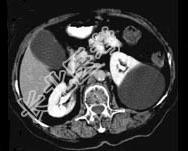

- 多项选择题女,38岁, 左腰部胀痛不适,CT平扫+增强如图所示, 下列说法正确的是 ( )

A、平扫时可见左肾一类圆形囊性病灶

B、病灶边界清晰,表面光整

C、增强扫描皮质期和实质期该病灶均未见强化

D、考虑为左肾囊性肾癌

E、考虑为左肾囊肿